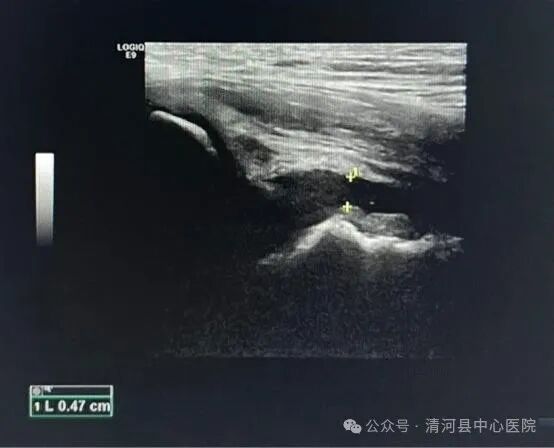

1、关节腔积液型:患侧股骨颈颈前间隙较健侧增宽大于1mm,前隐窝处有积液,伴或不伴滑膜增厚。